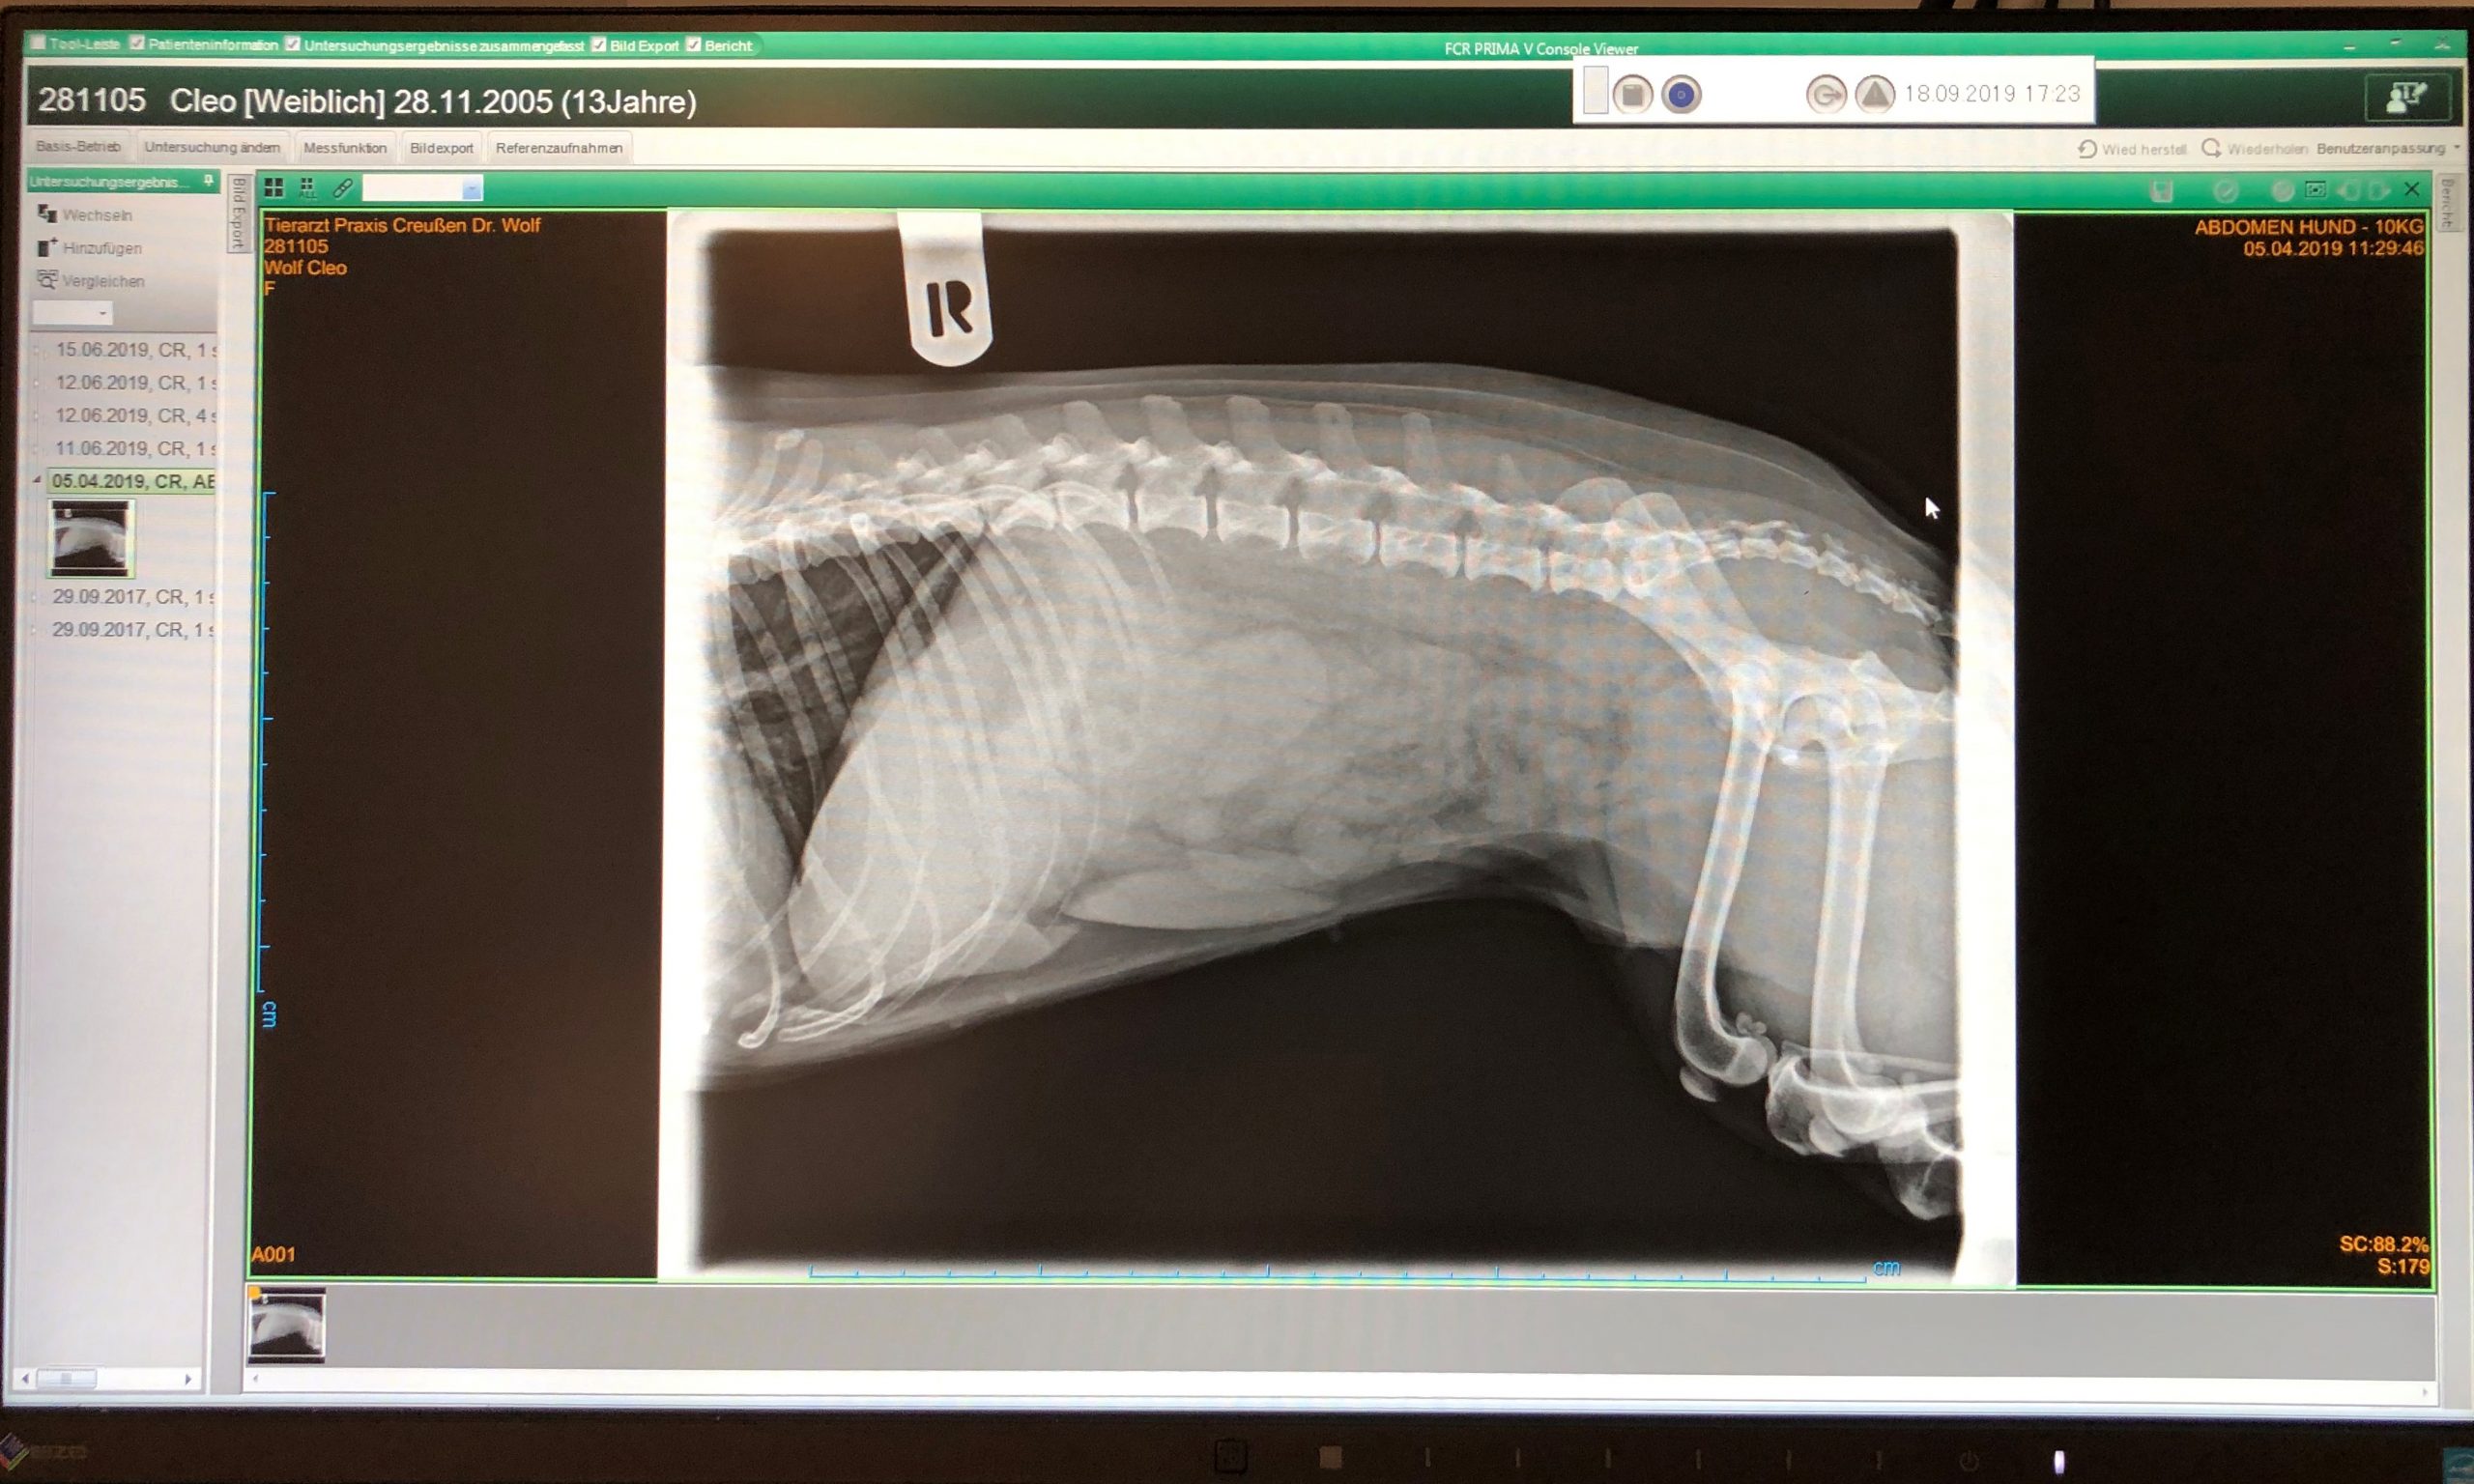

Digitales Röntgen